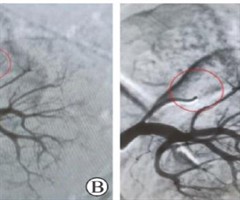

左侧副肾动脉假性动脉瘤破裂出血1例报告并文献复习

Rupture and hemorrhage of pseudoaneurysm in the left pararenal artery:a case report and literature review WU Chaoyue1’&#...